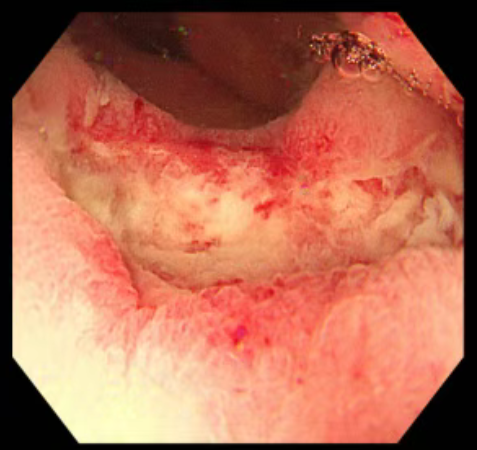

治疗后第一次复查,残留溃疡面

付出终有回报。经过数个周期的系统治疗,7月4日,肛肠科为刘爷爷肛诊时发现肿瘤已明显缩小、软化,甚至不易触及。9月25日,复查肠镜及病理显示原直肠肿瘤处仅见纤维组织增生和炎细胞浸润,未见明确肿瘤残留。乙状结肠的息肉也通过内镜下手术(CSP)顺利切除。